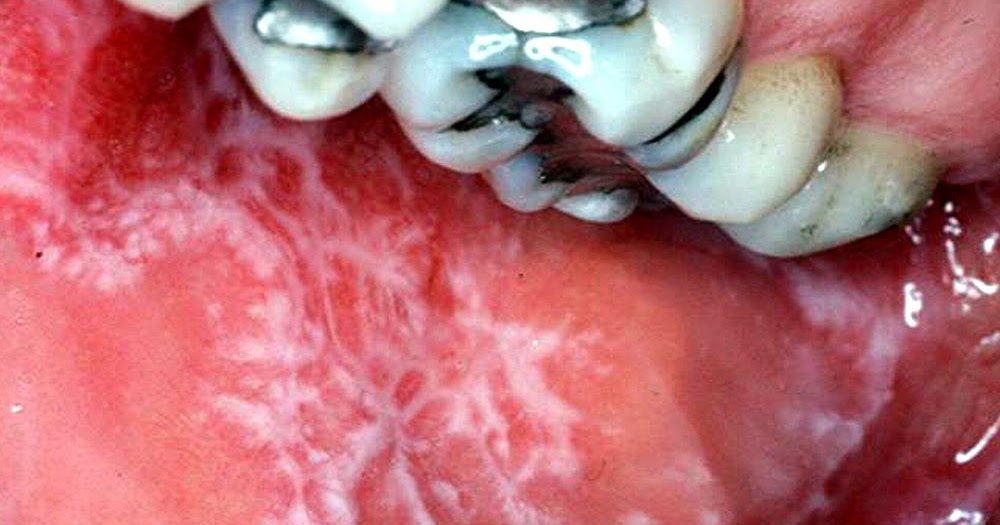

ORAL MEDICINE Smokeless Tobacco Lesions Directorio Source: directorioodontologico.info